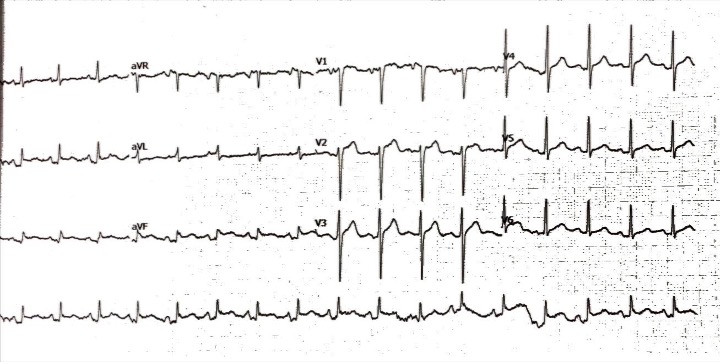

Relevant Test Results Prior to Catheterization

The initial electrocardiogram showed a sinus rhythm rate of 100 beat per minute with ST elevation in II, III and aVF. The transthoracic echocardiography demonstrated a left ventricular ejection fraction of 58% with inferior wall hypokinesia with no significant valvular abnormalities.